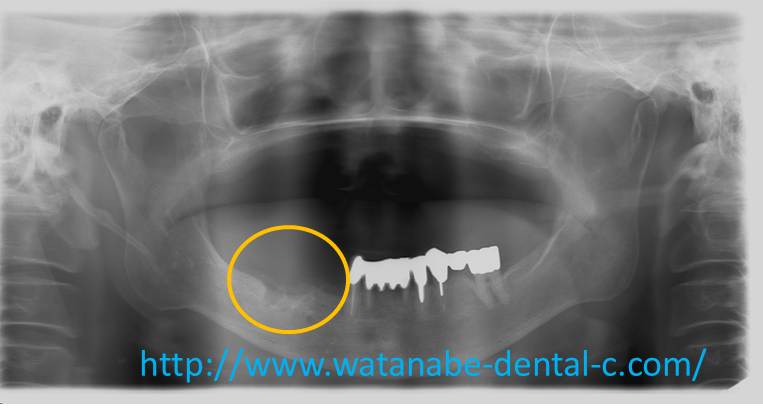

エックス線写真です。下顎管(神経と血管の通る管)とオトガイ孔を避けるように、右下4と6にインプラントを埋入する予定となりました。右下4は頬側にインプラント同時GBR,右下6は抜歯窩を利用して埋入と同時GBRを計画しました。